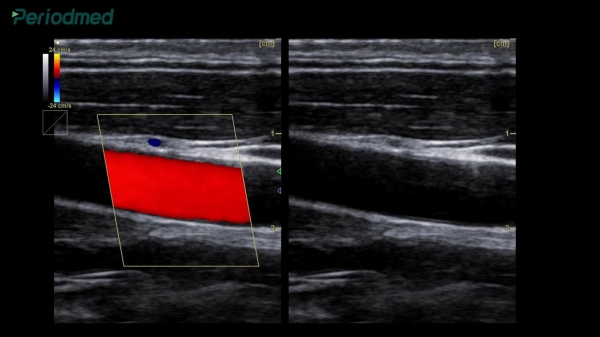

有意思的是,有研究者专门做了对照实验,让两组人分别吃普通面条和大量加醋的面条,半年后,加醋组的血管超声弹性明显下降,而且血脂、血压、口腔健康都有不同程度恶化。

这种直接对比,比单纯的理论更有说服力。科学数据面前,习惯不能任性。